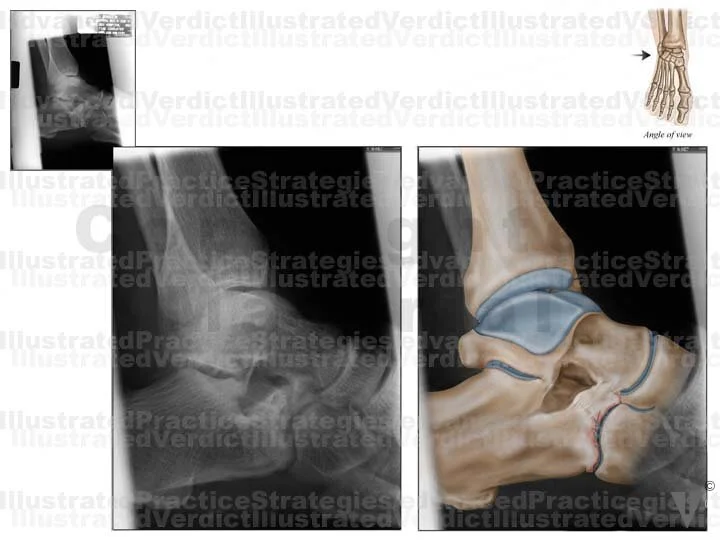

1. Original film

2. Original film with enhanced illustration